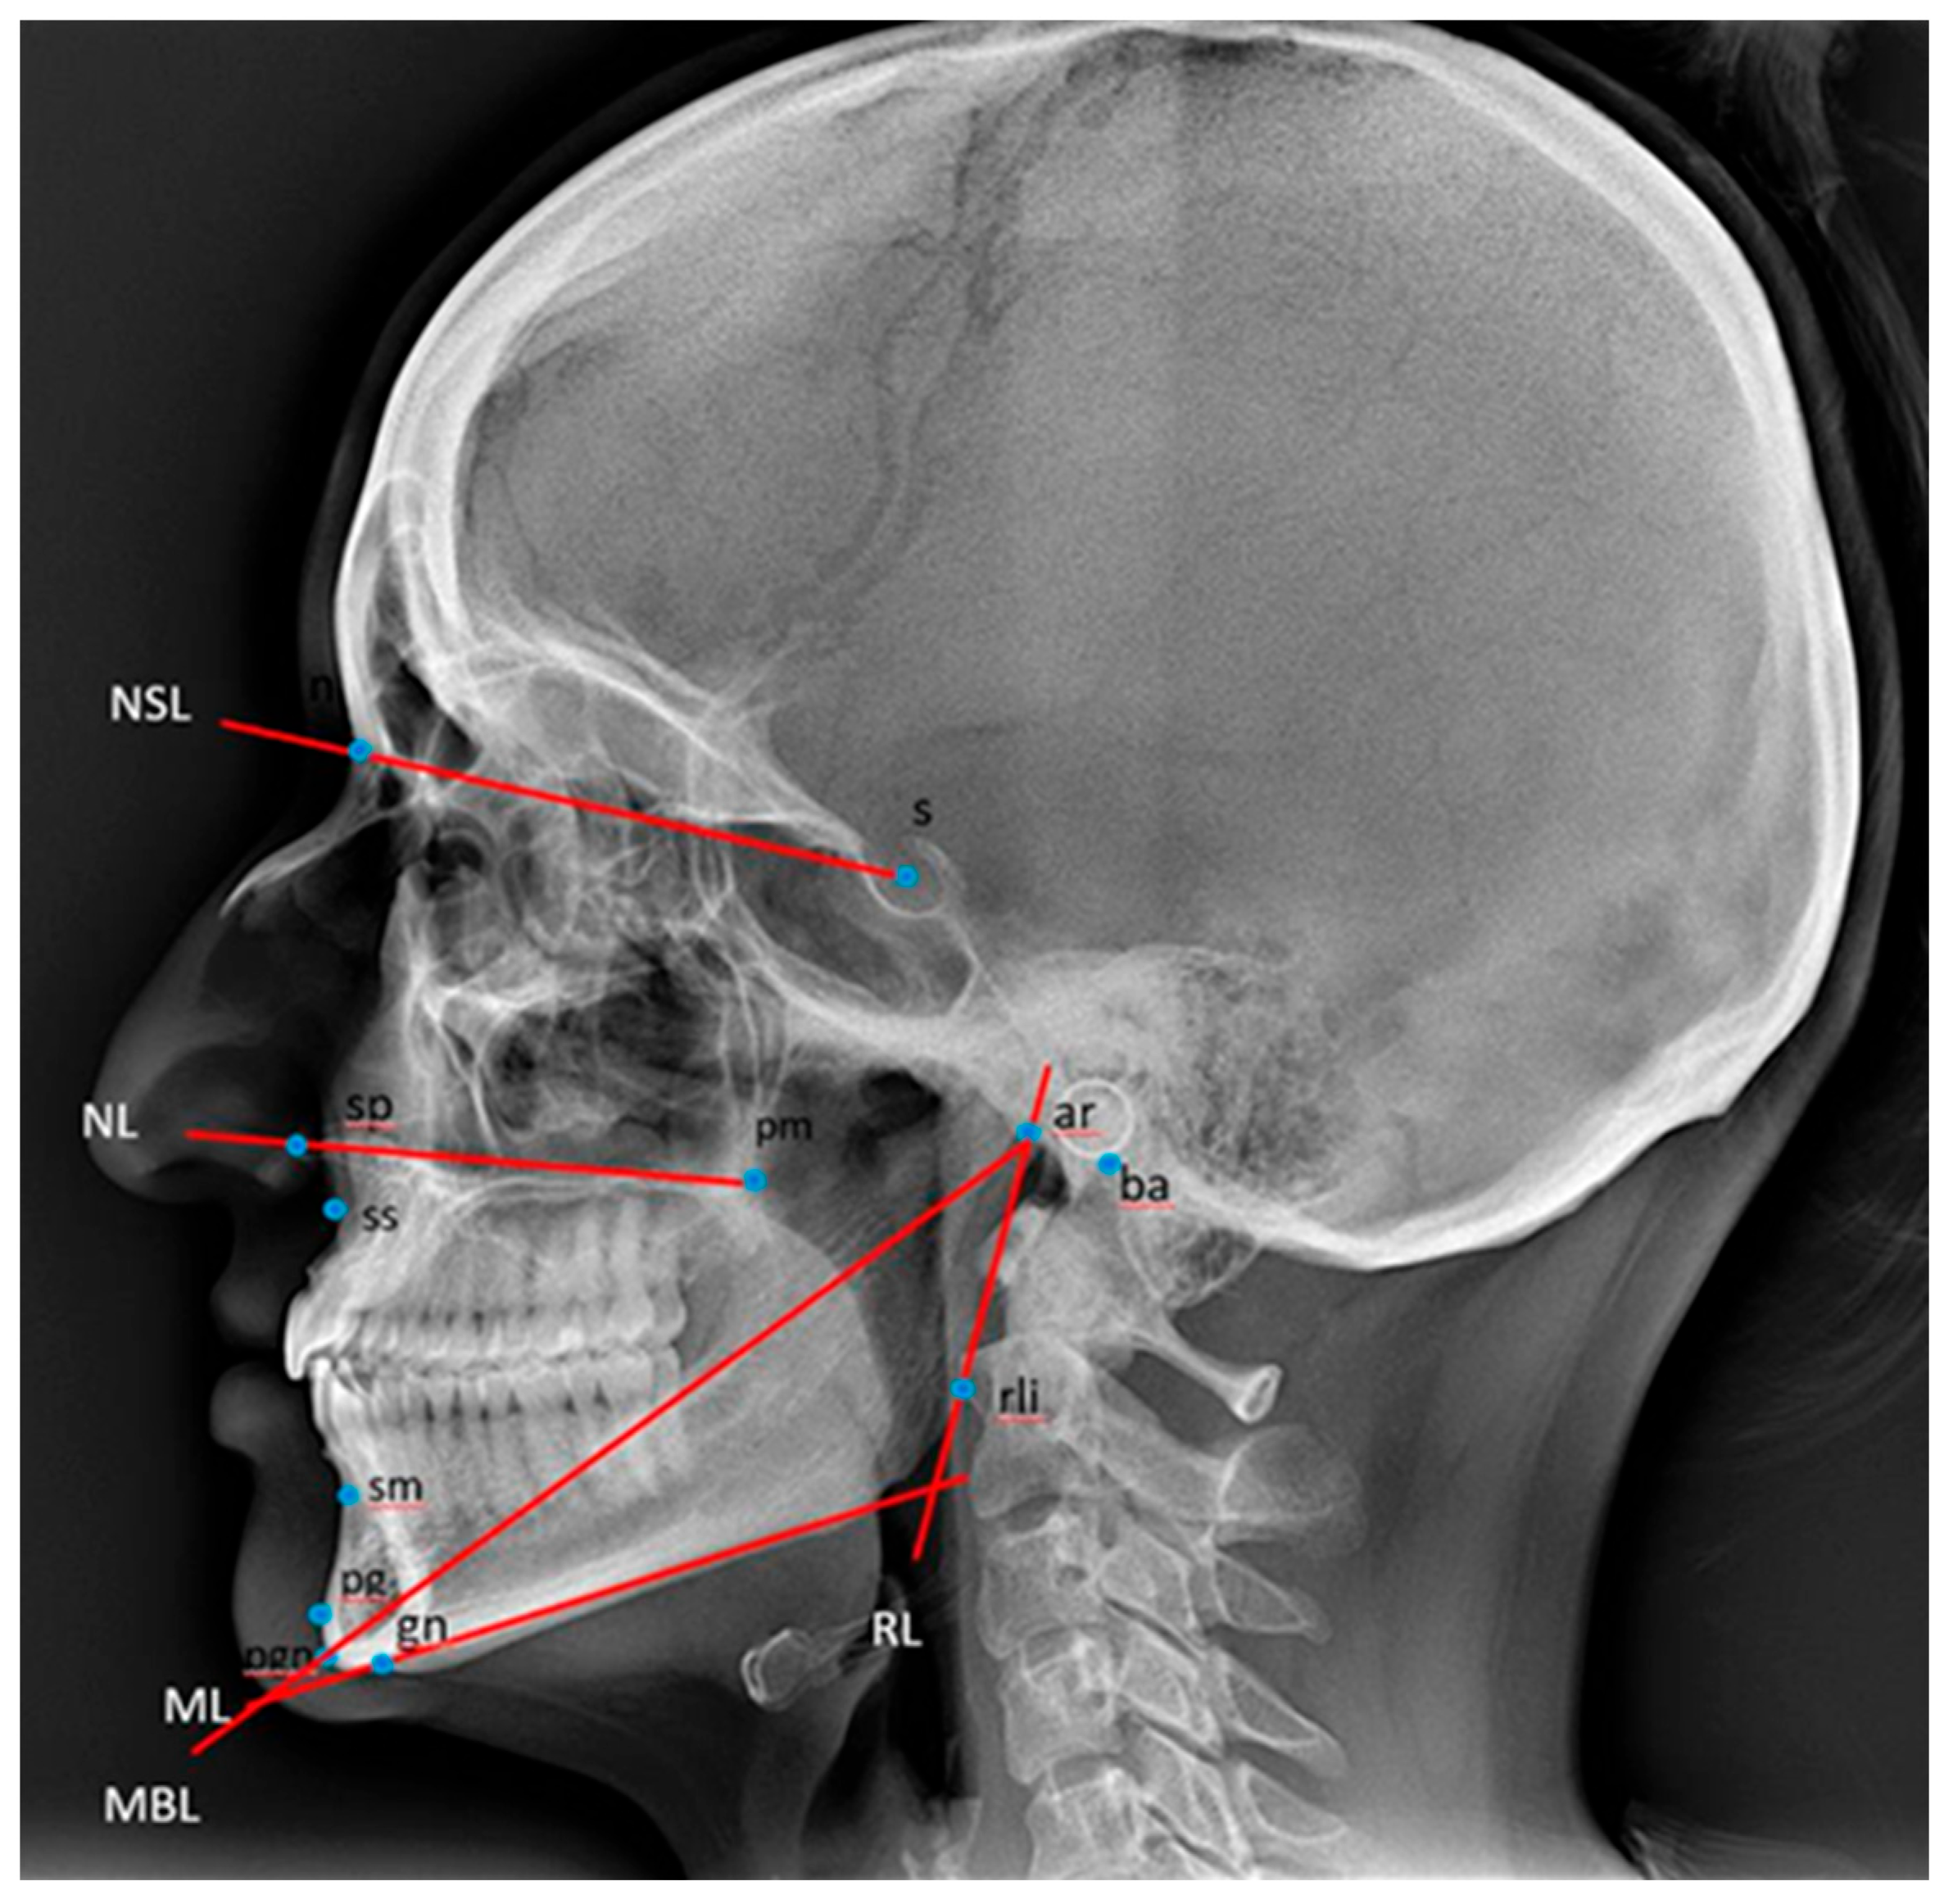

The cephalometric analysis was carried out according to Björk [27], and reference points and lines are described in Table 1 and illustrated in Figure 2.

Figure 2.

Reference points and lines used for the description of the craniofacial morphology [27]. ML: mandibular line, the tangent to the lower border of the mandible through gn. MBL: mandibular baseline, the line through pgn and ar. NL: nasal line, the line through sp and pm. NSL: nasion–sella line, the line through n and s. RL: ramus line, the tangent to the posterior border of the mandible. Ba: basion, the most postero-inferior point on the clivus. Ar: the point of intersection of the dorsal contours of the articular process of the mandible and the temporal bone. Gn: gnathion, the most inferior point on the mandibular symphysis. N: nasion, the most anterior point of the frontonasal suture. Pg: pogonion, the most anterior point of the mandibular symphysis. Pm: pterygomaxillare, the intersection between the nasal floor and the posterior contour of the maxilla. S: sella, the centre of the sella turcica, the upper limit of the sella turcica is defined as the line joining the tuberculum and the dorsum sellae. Sm: supramentale, the most posterior point on the anterior contour of the lower alveolar arch. Sp: spinal point, the apex of the anterior nasal spine. Ss: subspinale, the most posterior point on the anterior contour of the upper alveolar arch. Rli: ramus line inferior, the tangent point on the posterior border of the mandibular ramus to a line through ar. Pgn: Prognathion, the point on the mandibular symphysis with the maximum length from the condylion.